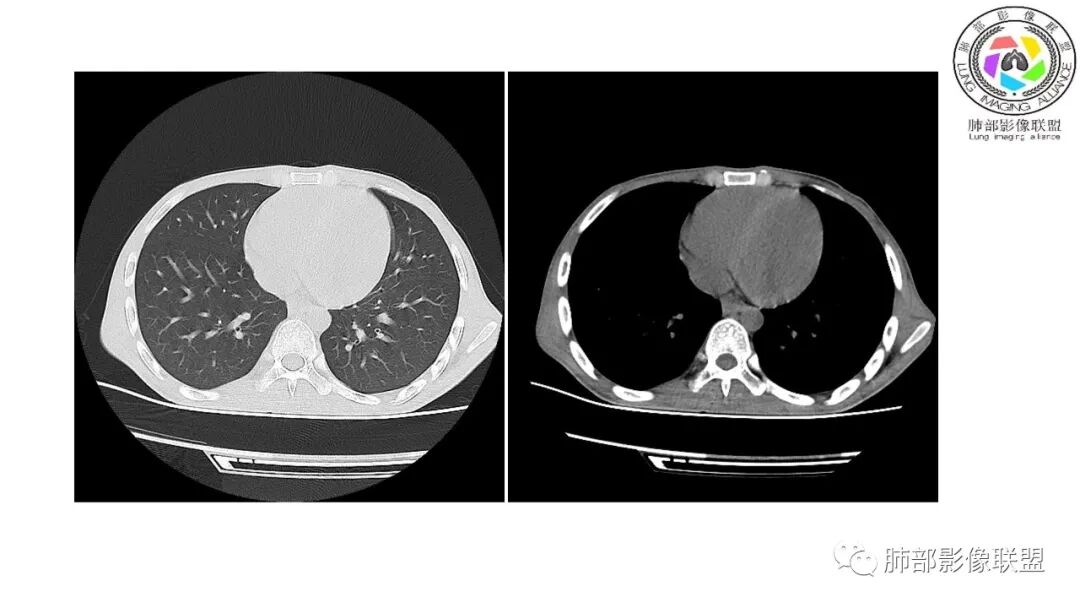

影像与临床:1.青年男性,HlV阳性,颜面部皮疹(未提供皮疹图像)、发热(高热),实验室CRP、PCT高,T-Spot阴性。2.右肺下叶空洞结节,壁厚不均,边界清楚,其内线状影,未见液平及钙化,未见卫星灶,纵隔淋巴结增大,双侧腋窝见增大淋巴结。心腔内低密度提示贫血可能。肝脾影增大,未见结节影及块影。腹膜后见多发增大淋巴结。

综合分析:本例肺部影像学改变并不具有特征性,空洞性病灶须与多种疾病鉴别,但年轻HIV阳性患者,高热,皮疹,肝脾增大,纵隔、腋窝、腹膜后见多发增大淋巴结等都强烈提示马尔尼菲篮状菌感染的可能性。